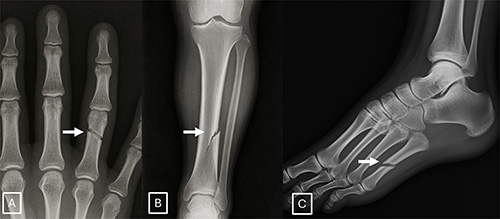

Images (JPG, TIF):

Figure 4. Examples of GPT-4o-generated radiographs of fractures: (A) posteroanterior radiograph of the hand, (B) posteroanterior radiograph of the lower leg, and (C) medial oblique radiograph of the foot. The images show fracture lines (arrow) that are unusually smooth, clean, and consistent and, in the case of B, unicortical. The presence of these idealized fracture lines, characterized by unnatural smoothness and incomplete cortical disruption, could serve as a primary diagnostic cue for identifying artificial intelligence–generated trauma images.